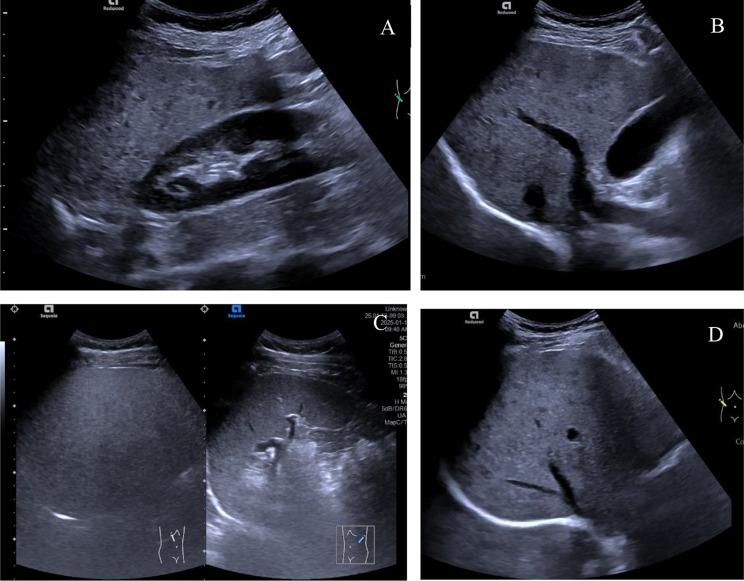

METHODS

This retrospective study involved 89 patients diagnosed with WD. The demographic characteristics, body mass index (BMI), conventional ultrasound examination, liver shear wave elastography, and ultrasound-derived fat fraction (UDFF) detection data were collected and statistically analyzed. The degree of hepatic steatosis was evaluated using the visual scoring method known as the Hamaguchi score. The Bland-Altman plot was used to analyze the intra-observer and inter-observer consistency of UDFF measurements. The Spearman correlation analysis was conducted to explore the correlations among BMI, UDFF, and the Hamaguchi score. Additionally, confounding factors were included to analyze whether UDFF was an independent influencing factor for WD hepatic steatosis. The receiver operating characteristic (ROC) curve was utilized to determine the cutoff value of UDFF for diagnosing WD hepatic steatosis and its diagnostic efficacy.